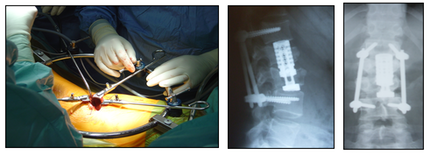

Рис. 7. Перкутанная ТПФ и вертебропластика L-I позвонка.

Рис. 8. Перкутанная ТПФ с аугментацией винтов и вертебропластика Th-ХI позвонка.